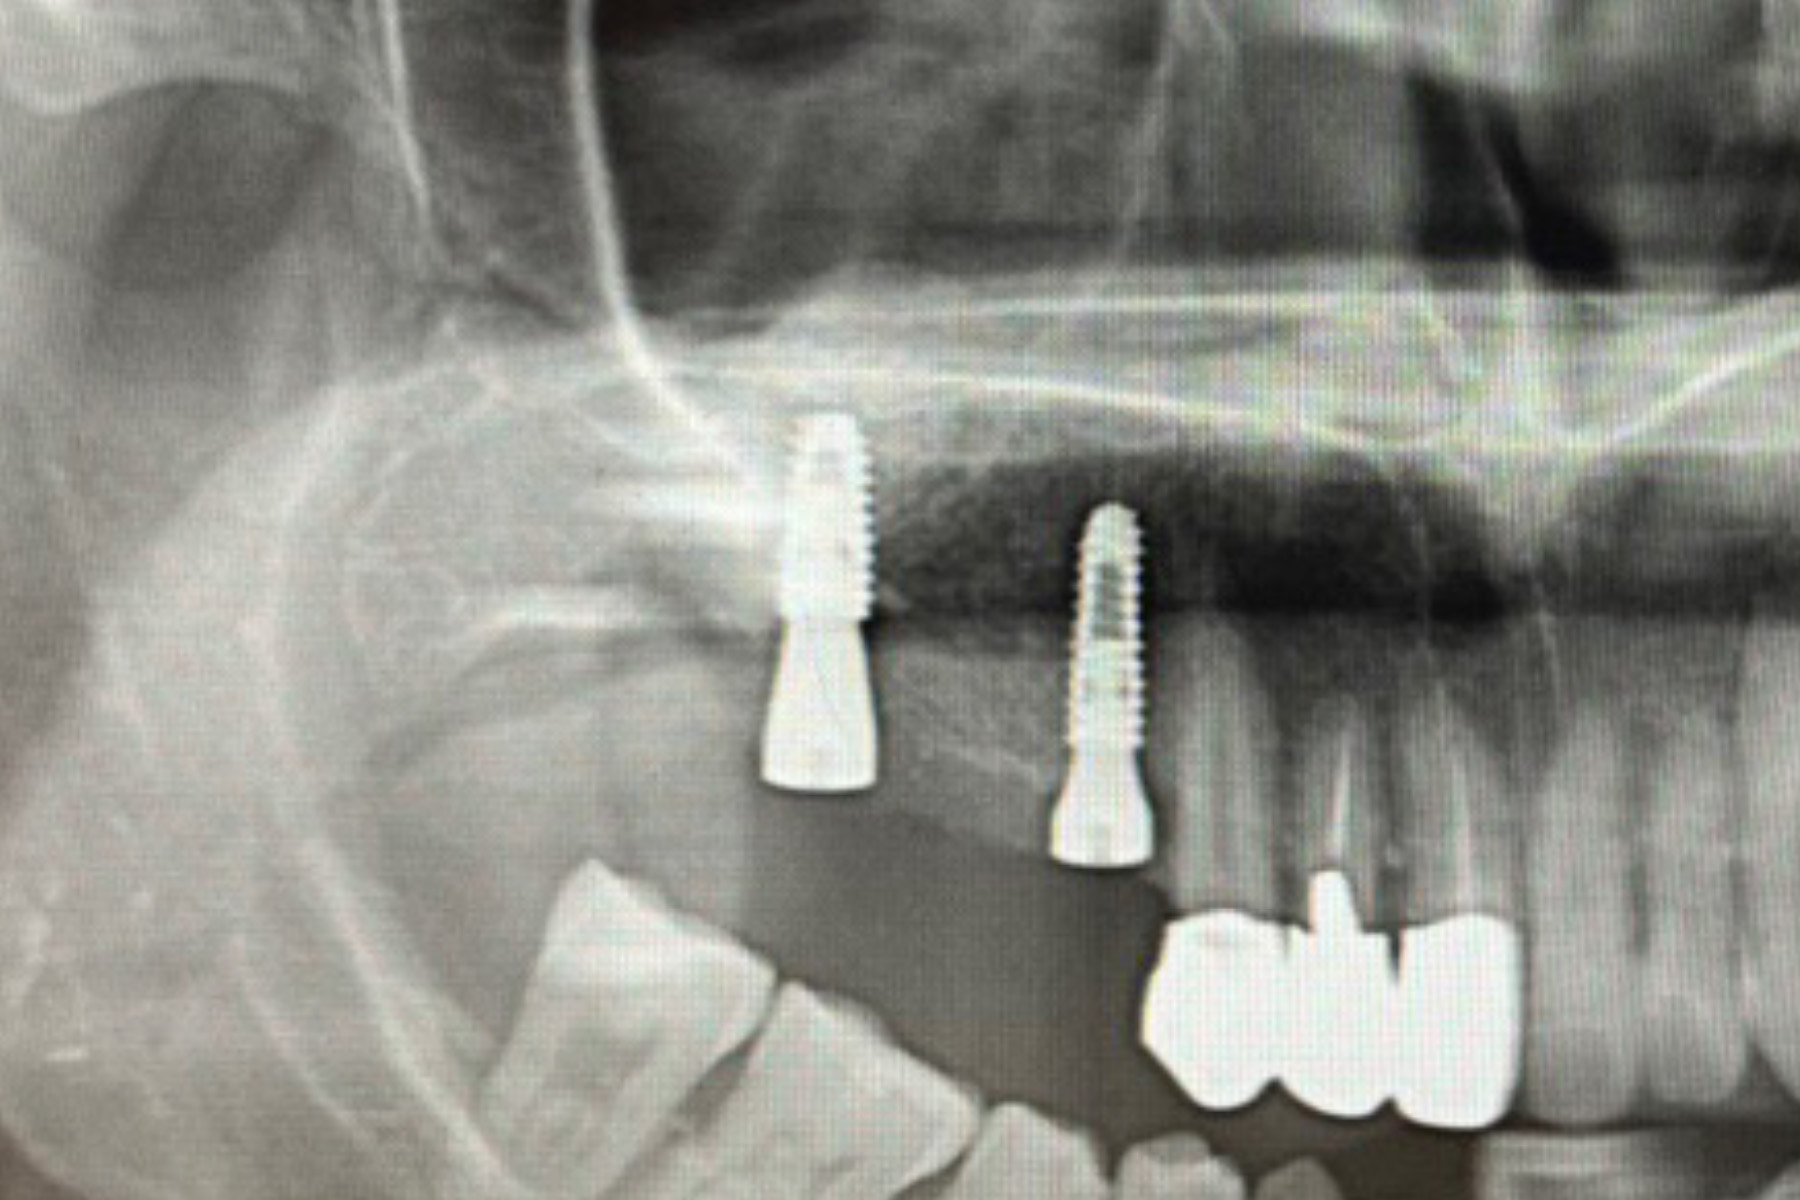

| 主訴 | 骨が薄くインプラントは出来ないと言われた |

| 治療内容 | 通常インプラントは約8〜10mmの長さであり骨の厚みもその程度無いと治療は不可能である。今回骨は1〜2mmで薄かった為骨を大規模に増やす手術を行い10mm以上の骨を造成した。治癒後インプラント埋入手術を可能な状態にした。 |

| 治療期間 | 6〜9ヶ月 |

| 治療費 | 約¥300,000(骨造成手術) |

| 治療リスク | 術後疼痛、腫脹、必要であれば再度骨造成を行う。 |